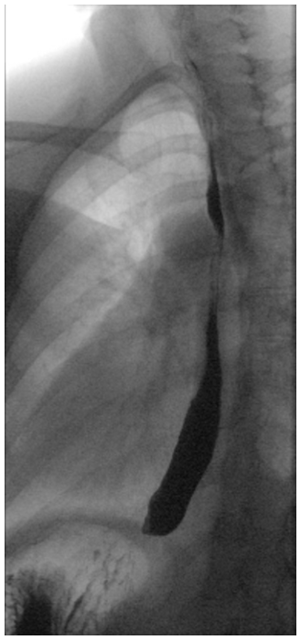

An esophagram is a video x-ray of the swallowing function in your esophagus, which is the tube that squeezes food and liquid from your throat to your stomach. If you have a problem in the function of your esophagus, you may have a variety of swallowing symptoms including feeling like food or pills stick in your chest and throat, chest pain during meals, regurgitation, and reflux.

If your doctor orders an esophagram, this will be done by a radiologist in the radiology department. You will drink a chalky contrast material called barium which lights up on x-ray. The doctor will film the barium traveling down your esophagus. The whole test is painless and noninvasive, and may last for 5-10 minutes. After the evaluation you will have a return appointment with your ENT doctor to discuss your test results.

| Example Esophagram X-rays | |